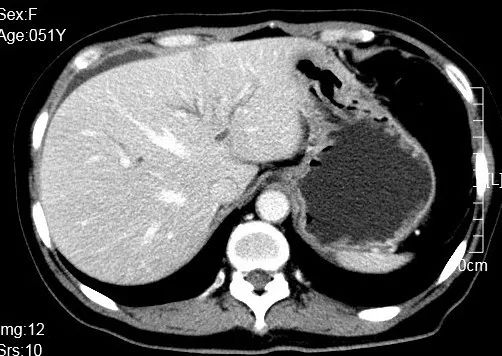

图1 患者腹部增强CT图像

增强CT显示(图1):肝内胆管轻度扩张,胆囊壁增厚,胆总管轻度扩张。